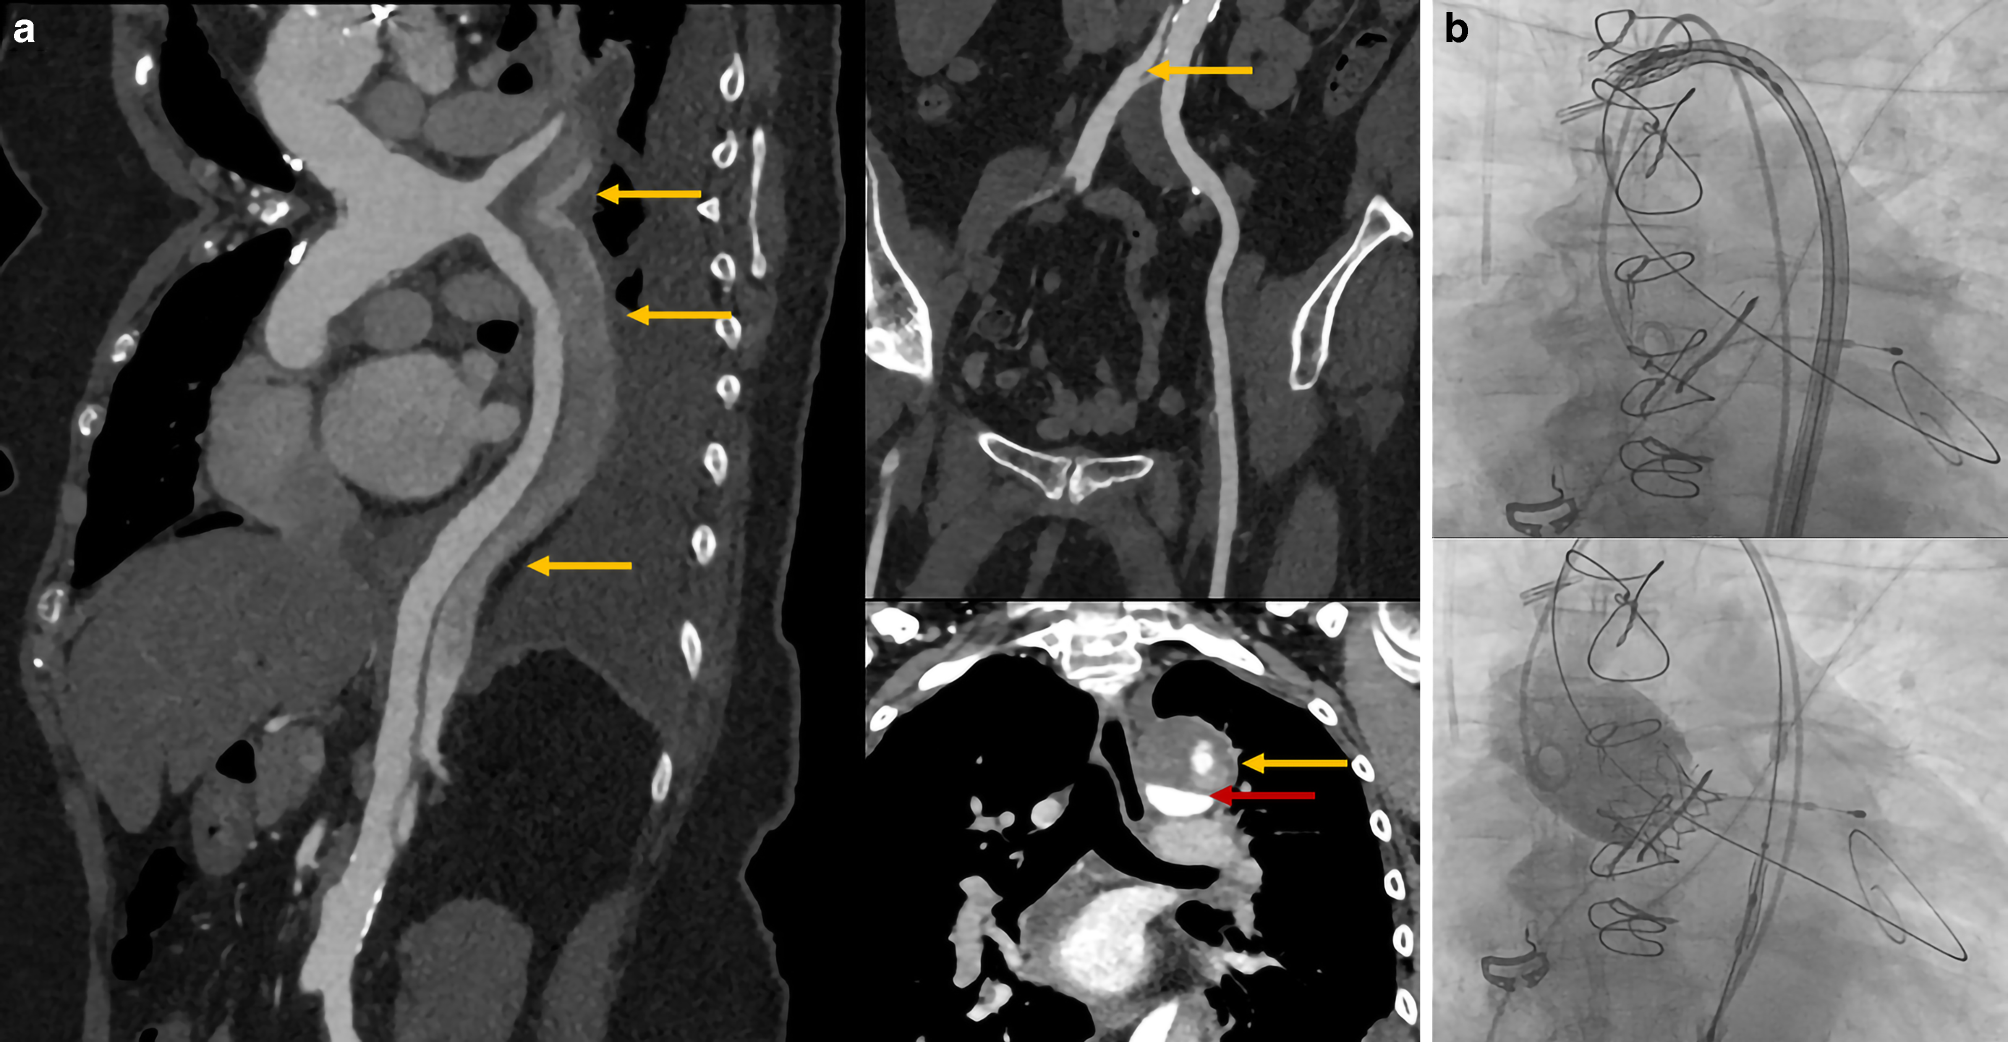

A 71-year-old woman was admitted to our hospital with progressive dyspnoea. She had a history of aortic dissection (DeBakey type I), which was treated with a biological Bentall procedure (Crown 23 mm) and hemiarch replacement in 2016. Echocardiography showed severe valve degeneration and acute deterioration in left ventricular function. Despite optimal medical treatment, she went into cardiogenic shock with multi-organ failure. Redo surgery was considered extremely high risk due to the chronic aortic dissection and ongoing cardiogenic shock (Fig. 1a). Therefore, we performed salvage transfemoral valve-in-valve transcatheter aortic valve implantation (TAVI) under local anaesthesia. An Edwards Sapien 3 Ultra 23-mm valve was successfully implanted without any procedural complications (Fig. 1b). Haemodynamics improved immediately after valve deployment, and after a few days, the patient was discharged home.

Fig. 1

a Preprocedural computed tomography scans showing chronic aortic dissection extending into left proximal carotid artery and left subclavian artery, left renal artery and both common iliac arteries (all indicated by yellow arrows). Red arrow indicates true lumen of aortic arch. b New valve was passed through dissected aortic arch as operators gave traction on guide wire to make sure inner curve was followed. New valve was implanted without any complications